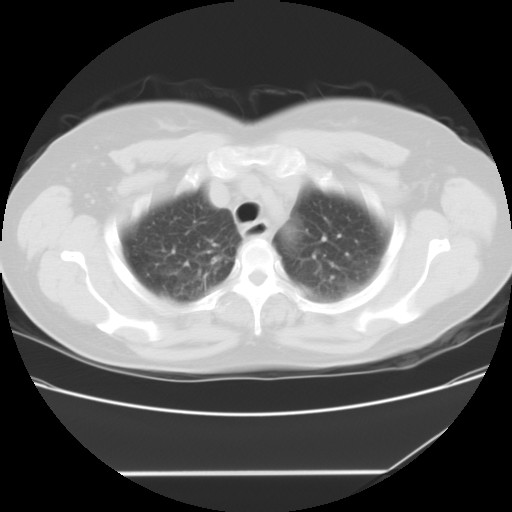

标题: CT24018:女性,62岁,咳嗽4年,无热,胸部CT扫 [打印本页]

女性,62岁,长期咳嗽,既往从事工作有粉尘接触,有高血压病史,110/150mmhg,近日咳嗽加重,脸面浮肿,请大家帮看下,

1、尘肺;2、慢性支气管炎合并肺部感染;3、心影增大(左房、左室大),考虑高血压性心脏病。

慢支并肺部炎症;右肺结核球?主肺动脉、右肺动脉影不宽,右心室不大,不支持肺心病;无心包积液。

间质性肺炎,有纤维化趋势。

1)慢性支气管炎并肺部感染、肺气肿。2)肺间质纤维化。

间质性肺炎,左下肺机化性肺炎。